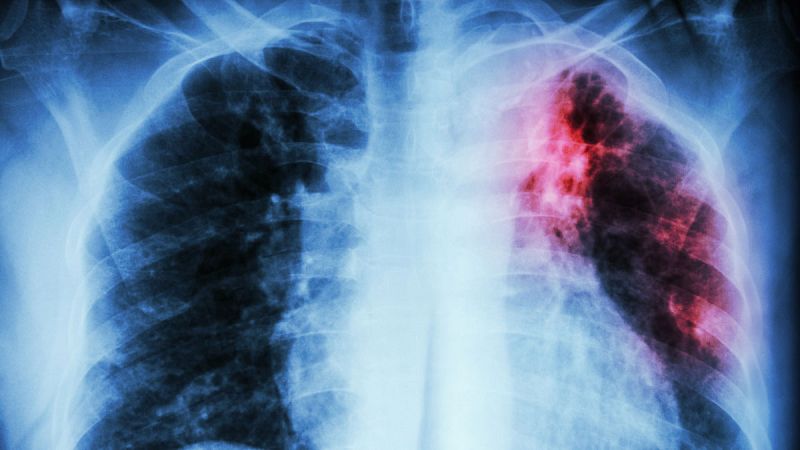

Se espera que más de siete millones de personas en Sudán del Sur se encuentren este verano en una situación de inseguridad alimentaria aguda o peor. Los pacientes de tuberculosis y VIH enfrentan un riesgo mayor, ya que la intensidad del tratamiento es muy difícil de soportar con el estómago vacío y deben elegir entre soportar fuertes dolores o suspender su medicación y arriesgarse a morir.

Muchos pacientes de VIH y tuberculosis en Sudán del Sur se enfrentan al dilema de elegir entre medicarse y sufrir fuertes dolores y mareos o abandonar la medicación y arriesgarse a morir de su afección. En algunos casos, el tratamiento puede incluir hasta ocho pastillas al día y alargarse durante toda la vida; un proceso que los pacientes deben afrontar con el estómago prácticamente vacío, debido a la grave situación de desnutrición en el país.

Como resultado, la desnutrición se extiende por toda la población, creando un círculo vicioso para los pacientes de VIH y tuberculosis, ya que no solo empuja a los pacientes a dejar la medicación, sino que también aumenta el riesgo de mortalidad de los pacientes al reducir considerablemente sus defensas inmunitarias.

La desnutrición aumenta el riesgo de mortalidad de los pacientes al reducir sus defensas inmunitarias.

“La inseguridad alimentaria se está convirtiendo en un problema”, explica el jefe del equipo médico de Médicos Sin Fronteras en Leer Daniel Mekonen. "Tenemos más de 600 pacientes coinfectados de tuberculosis y VIH, y muchos de ellos nos dicen que ya no pueden seguir el tratamiento adecuadamente por falta de alimentos. Lo reducen o lo interrumpen hasta que la situación mejora", detalla.

Cada vez recibimos más pacientes en fase avanzada, en estado grave, que se vuelven muy difíciles de tratar

Una decisión que, como agrega Mekonen, tiene consecuencias. "Cada vez recibimos más pacientes en fase avanzada, en estado grave, que se vuelven muy difíciles de tratar. Otros desarrollan resistencia a los antimicrobianos. Antes veíamos ocho pacientes nuevos al mes, pero últimamente esa cifra se ha duplicado y ha ascendido hasta los 16. Si no se ayuda a la gente con alimentos, nuestro programa no tendrá éxito", alerta.